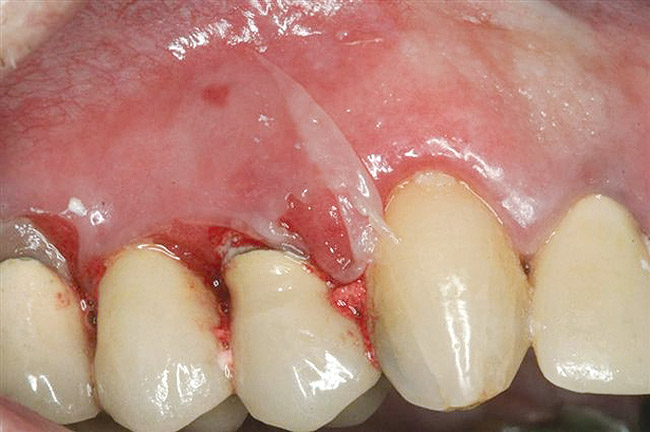

The oral cavity often is affected early in the disease process and, on occasion, may be the only site of involvement.59 Le­sions most often are seen on the buccal mucosa, palate, tongue, and lips. They manifest as quickly bursting blisters, leading to erosions and ulcer formation (Figure 11). Gingival lesions may appear first as isolated blisters or areas of tissue sloughing, but, as the condition progresses, severe DG may occur60 (Figure 12). Nikolsky’s sign is prominent, and lesions sometimes may remain confined to the gingiva61 (Figure 13).

Figure 12  Oral presentation of PV on the gingival.

Figure 12